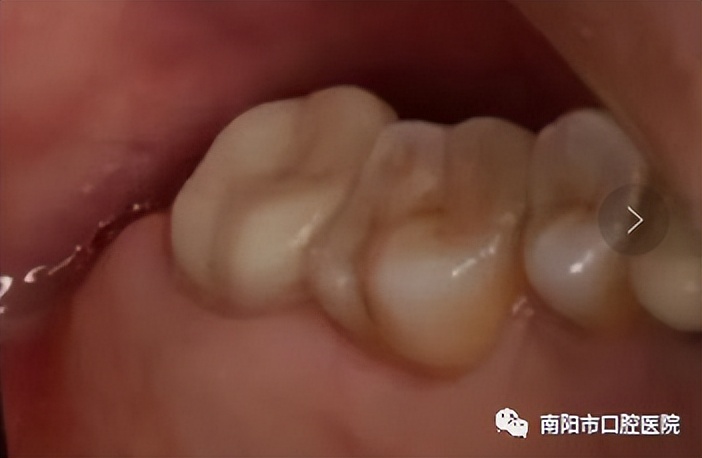

拔除后种植牙修复